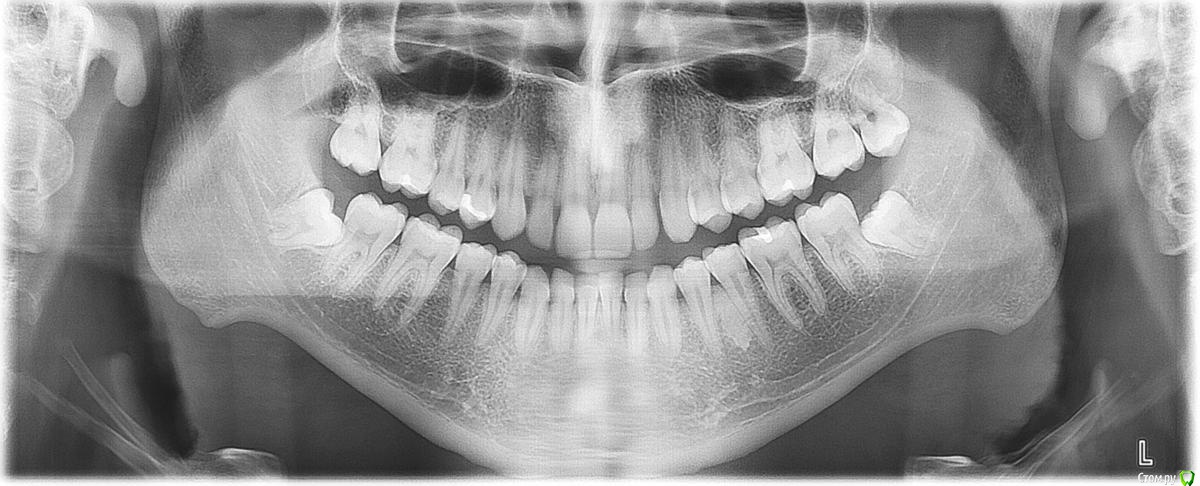

bogdan_r Опубликовано 9 июля, 2015 Поделиться Опубликовано 9 июля, 2015 (изменено) Здравствуйте. Делал себе ОПТГ и меня смутили неровные края и выступы в углах нижней челюсти. Скажите, это нормально? Какие возможны последствия? Изменено 9 июля, 2015 пользователем bogdan_r Ссылка на комментарий

red_butler Опубликовано 9 июля, 2015 Поделиться Опубликовано 9 июля, 2015 это просто строение вашей челюсти 1 Ссылка на комментарий